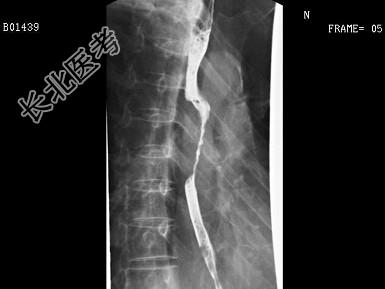

- 单项选择题女,58岁, 吞咽困难半年,结合图像, 最可能的诊断为 ( )

A、正常食管

B、食管静脉曲张

C、食管癌

D、食管憩室

E、食管平滑肌瘤